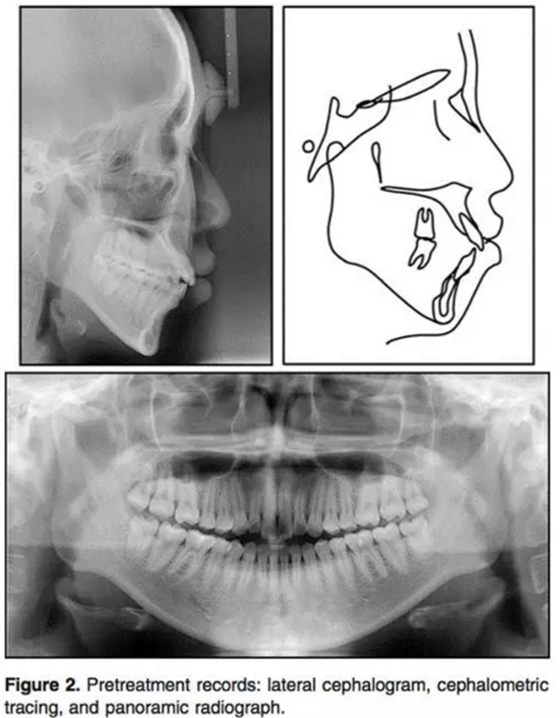

輔助檢查:側(cè)位片:骨性II類(ANB3.5°);下頜后縮(N per to Pog,-4.5°);高角(PFH/AFH, 59.5%; MP-FH, 32.7°)。上頜切牙輕微前突,下頜切牙突度正常(U1 to FH, 120.7°;IMPA, 90.0°)。上頜前后牙都垂直向發(fā)育過度(U1-PP, 36.9 mm; U6-PP, 27.9mm) 。上前牙在休息位時暴露量相對過量(U1 to stomion, 4.8 mm) 。咬合平面角正常(OP to FH, 12.8°)。此外,下頜垂直向高度也長于正常值 (L1 to mandibular plane, 47.7 mm; L6 to mandibular plane, 37.0 mm;Table 1) 。